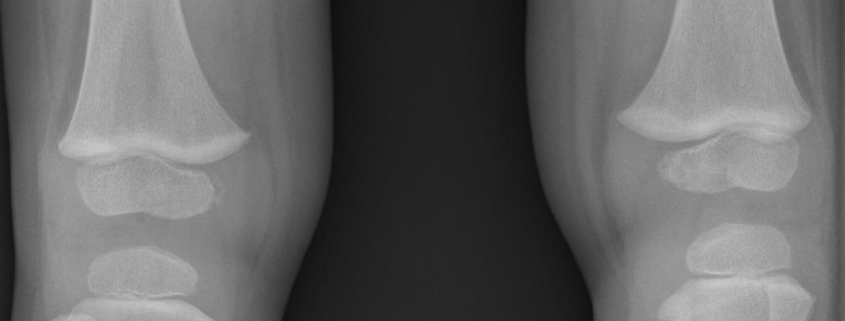

Blount’s disease is typically diagnosed through a combination of physical examinations, medical history, and imaging tests, such as x-rays or MRI. Your doctor will look for signs of leg bowing and may measure the angle of the bowing to confirm the diagnosis.